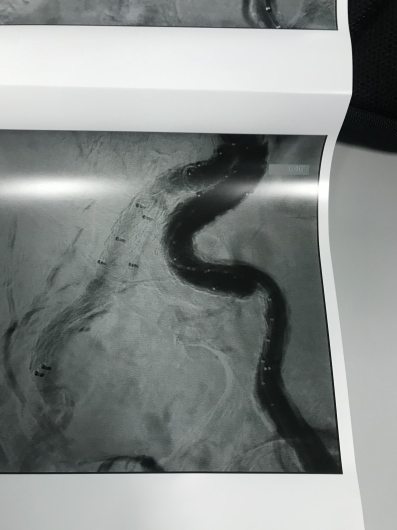

Dirigente Medico di ruolo presso U.O.C. Chirurgia Vascolare ed Endovascolare Ospedale San Giovanni di Dio e Ruggi d’Aragona di Salerno. Pratica attività ambulatoriale, laboratorio di diagnostica ultrasonografica, diagnostica angiografica e attività di sala operatoria (chirurgia open ed endovascolare). L’attività chirurgica tradizionale ed endovascolare comprende il trattamento delle lesioni stenotiche/ostruttive dei tronchi sovraortici (carotidi), lesioni stenotiche/ostruttive delle arterie periferiche e viscerali, degli aneurismi dell’aorta e aneurismi periferici e viscerali (sia in elezione che in urgenza), inoltre l’attività chirurgica comprende il trattamento della patologia venosa (vene varicose/varici) secondo le tecniche chirurgiche classiche (es. stripping) e moderne (laser, radiofrequenza, scleroterapia maggiore), scleroterapia minore di teleangectasie e vene reticolari (estetica vascolare).